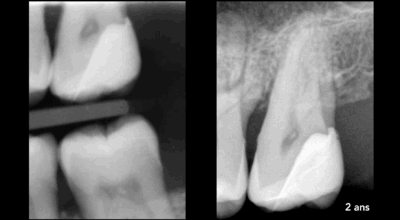

Direct pulp capping

If removal of the carious lesion (middle diagram) extends to the dental pulp, a bioactive biomaterial (such as a bioceramic cement) can be placed directly over the exposed pulp.

Right-hand diagram: 1 = bioactive biomaterial such as bioceramic cement, 2 = coronal restorative biomaterial

Direct pulp capping: 90.4% success rate